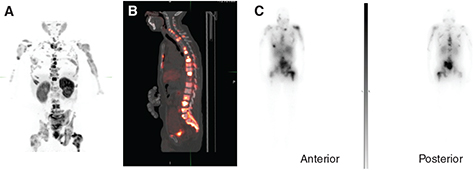

Post-therapy scintigraphy can be performed at a single time point after 177Lu-PSMA RLT administration or at multiple points in a serial fashion, typically ranging from 120 minutes to 8 days post-injection (Figure 3). Post-therapy scintigraphy can be performed by planar imaging or single photon emission computed tomography (SPECT). A significant disadvantage of planar imaging compared to SPECT/CT is its inaccuracy in distinguishing between overlapping areas of radiotracer uptake present in more than one organ, which most likely results in dose overestimation.

Fig 3

Figure 3. A 57-year-old male with mCRPC. A, 68Ga-PSMA PET-CT Maximum intensity projection (MIP) image shows widespread intensely PSMA avid osseous lesions in the axial and appendicular skeleton. B, Fused sagittal image showing multiple intensely PSMA avid sclerotic lesions in the spine. C, PSMA post-therapy emission planar images (anterior and posterior) acquired 7 days after the therapy show PSMA-avid osseous lesions in the axial and appendicular skeleton with a distribution similar to the PSMA PET/CT.